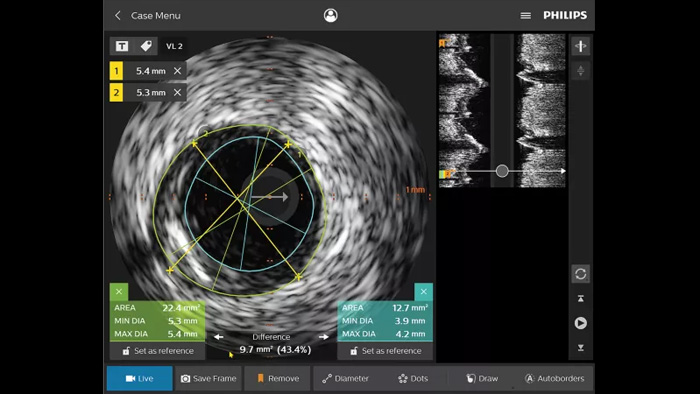

IVUS Devices

Der intravaskuläre Ultraschall (IVUS) ist eine katheterbasierte Bildgebungstechnologie, mit der Blutgefäße von innen nach außen visualisiert werden können, um das Vorliegen und das Ausmaß der Erkrankung zu beurteilen. IVUS unterstützt die Entscheidungsfindung, die Führung und die Bestätigung der richtigen interventionellen Behandlung für jeden einzelnen Patienten.

IntraSight

ein Screenshot eines medizinischen Geräts

IntraSight liefert durch iFR/FFR- und IVUS-Modalitäten in Verbindung mit dem Angiogramm mehr Informationen und kann über den Touchscreen am Tisch gesteuert werden. IntraSight ist auf einer Basisplattform aufgebaut, die eine schnelle Integration neuer Innovationen in Ihr Labor erlaubt.